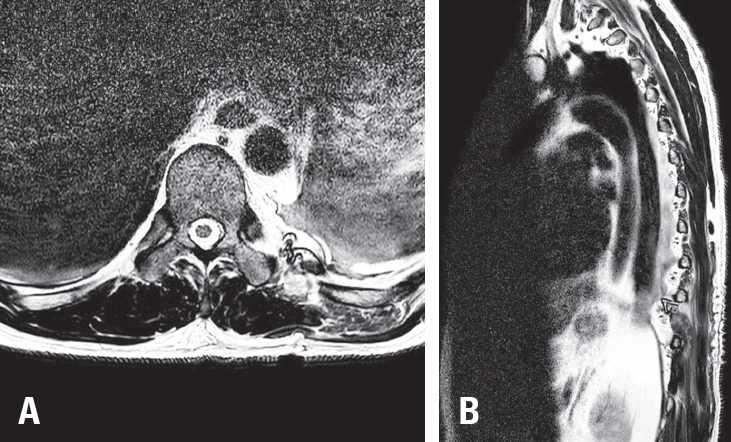

Magnetic resonance imaging (MRI) demonstrated a 2.8 cm ovoid, hypervascular mass at the T10–T11 level in the left posterior hemithorax, encasing the left 10th rib and adjacent to the left T10 transverse process. The mass showed hypointensity on T1-weighted images (

Fig. 1A), hyperintensity on T2-weighted images (

Fig. 1E,

F), and homogeneous enhancement after contrast administration (

Fig. 1B-

D). Based on these imaging characteristics, the lesion was initially suspected to be a schwannoma, and surgical resection was planned.

Fig. 1.Preoperative magnetic resonance imaging (MRI) of the thoracic spine. (A) Axial T1-weighted image showing a hypointense mass at the left T10–11 level. (B) Axial T1-weighted dolinium-enhanced image demonstrating homogeneous enhancement. (C) Coronal T1-weighted gadolinium-enhanced image showing the ovoid mass in the left posterior hemithorax. (D) Sagittal T1-weighted gadolinium-enhanced image delineating the extent of the mass. (E) Axial T2-weighted image showing a hyperintense lesion. (F) Sagittal T2-weighted image confirming hyperintensity of the mass.